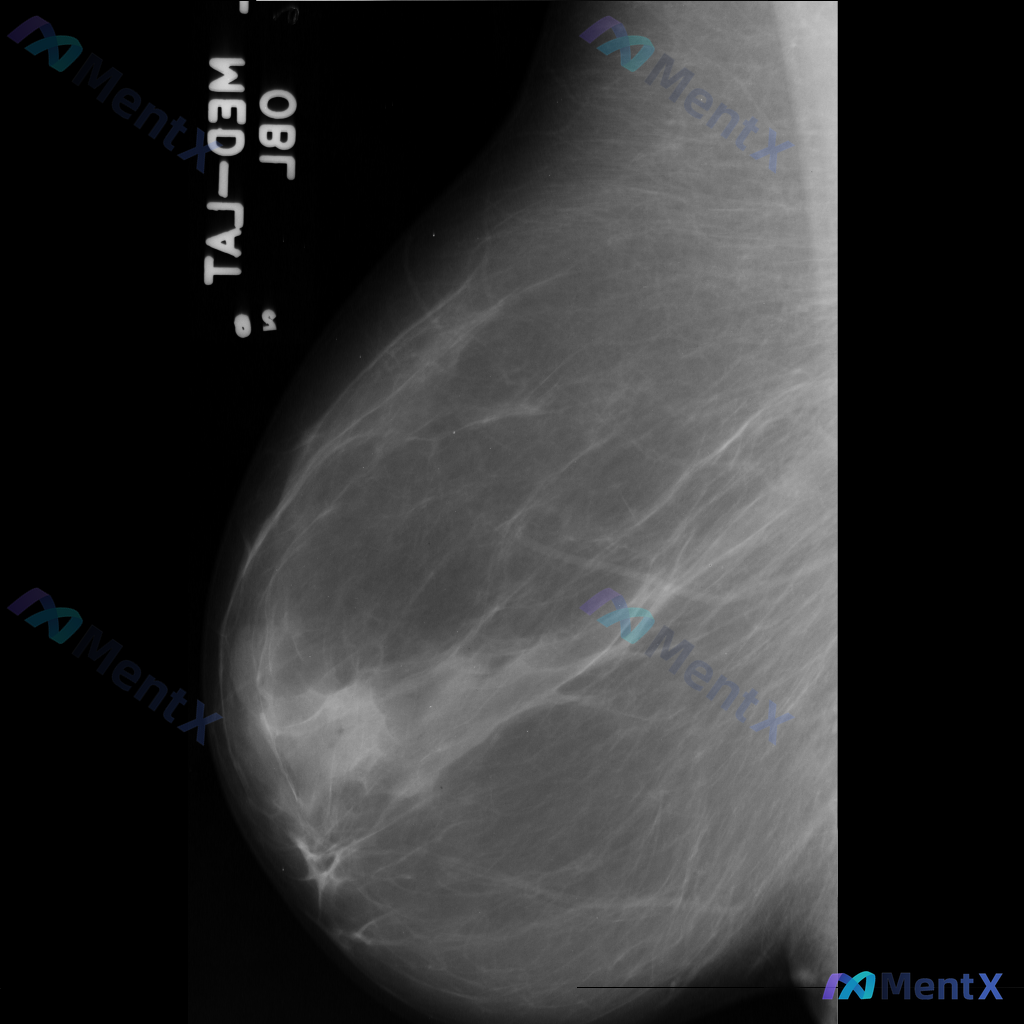

整理到一份乳腺钼靶影像资料,主要表现如下: - 乳腺中后部可见局灶性结构扭曲 - 无明确的肿块核心 - 周围腺体和脂肪界面被不规则牵拉 目前暂不提供既往影像对比和详细病史(手术史、外伤史、炎症史等)。 这种表现大家会先怎么判断?更倾向于往哪种方向考虑?

整理到一份乳腺钼靶的影像资料,想和大家讨论一下: - 钼靶所见:左侧乳腺中央偏下区域存在局限性结构扭曲,表现为纤维腺体组织排列紊乱、牵拉;未见明确的肿块或钙化灶。 - 背景:乳腺密度较高,属于不均匀致密型或极度致密型(ACR B或C型)。 目前这种结构扭曲的表现,大家会先往哪个方向考虑?下一步的评估...